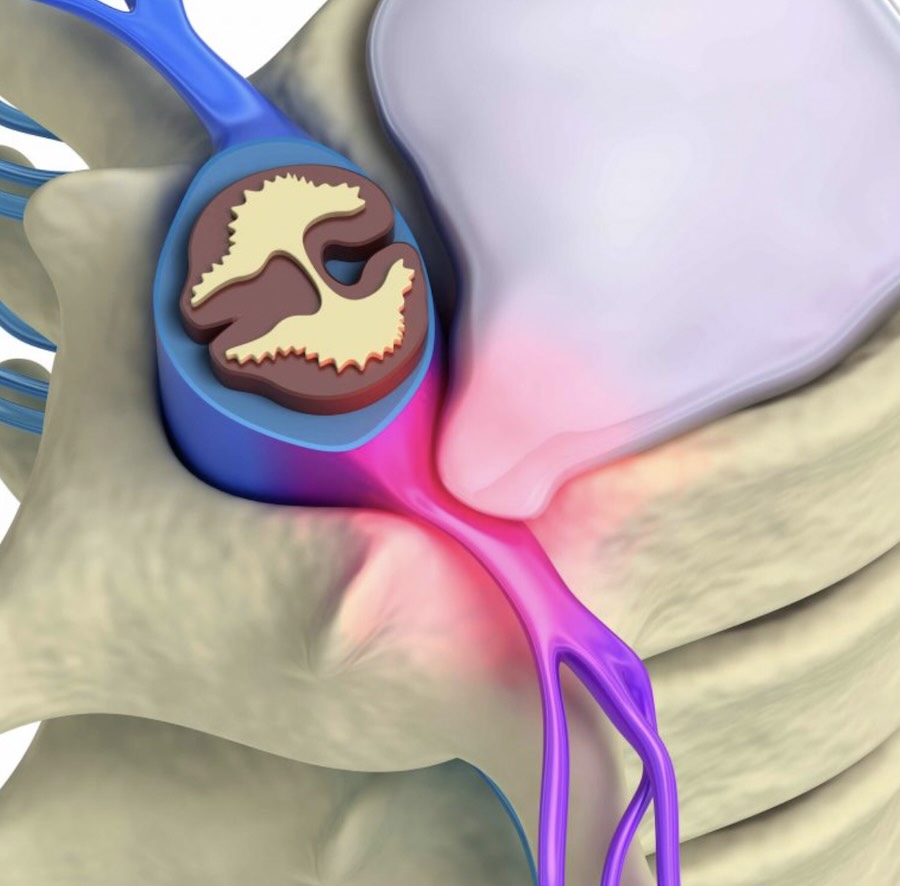

The discs between your vertebrae can sometimes bulge or shift, placing pressure on nearby nerves. When that happens, pain may travel down your leg—often called sciatica—and may include tingling or weakness.

Most disc-related problems don’t require surgery and can improve with careful, staged chiropractic treatment that reduces pressure and restores movement.

When a spinal nerve becomes irritated or compressed, pain may travel down the leg.

Typical symptoms include sharp or burning pain, numbness, tingling, or weakness following a nerve pathway.